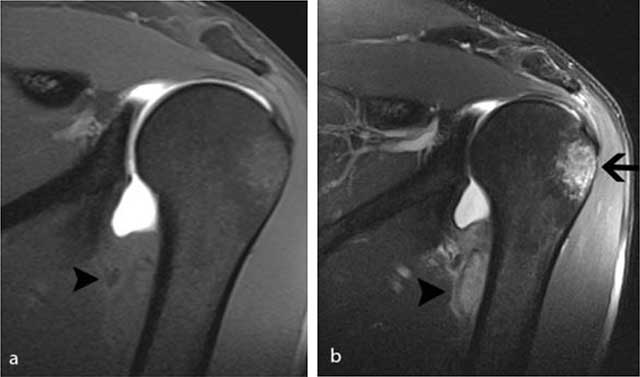

Figure 2

MR arthrography of the left shoulder performed four weeks after initial injury. a) On the coronal FS T1-WI, there is an extra-articular lesion with slightly inhomogeneous signal intensity (black arrowhead) at the medial side of the humeral diaphysis. b) The lesion (black arrowhead) is better seen on the FS T2-WI. Note also the posttraumatic bone marrow edema (black arrow) at the superolateral aspect of the humeral head.